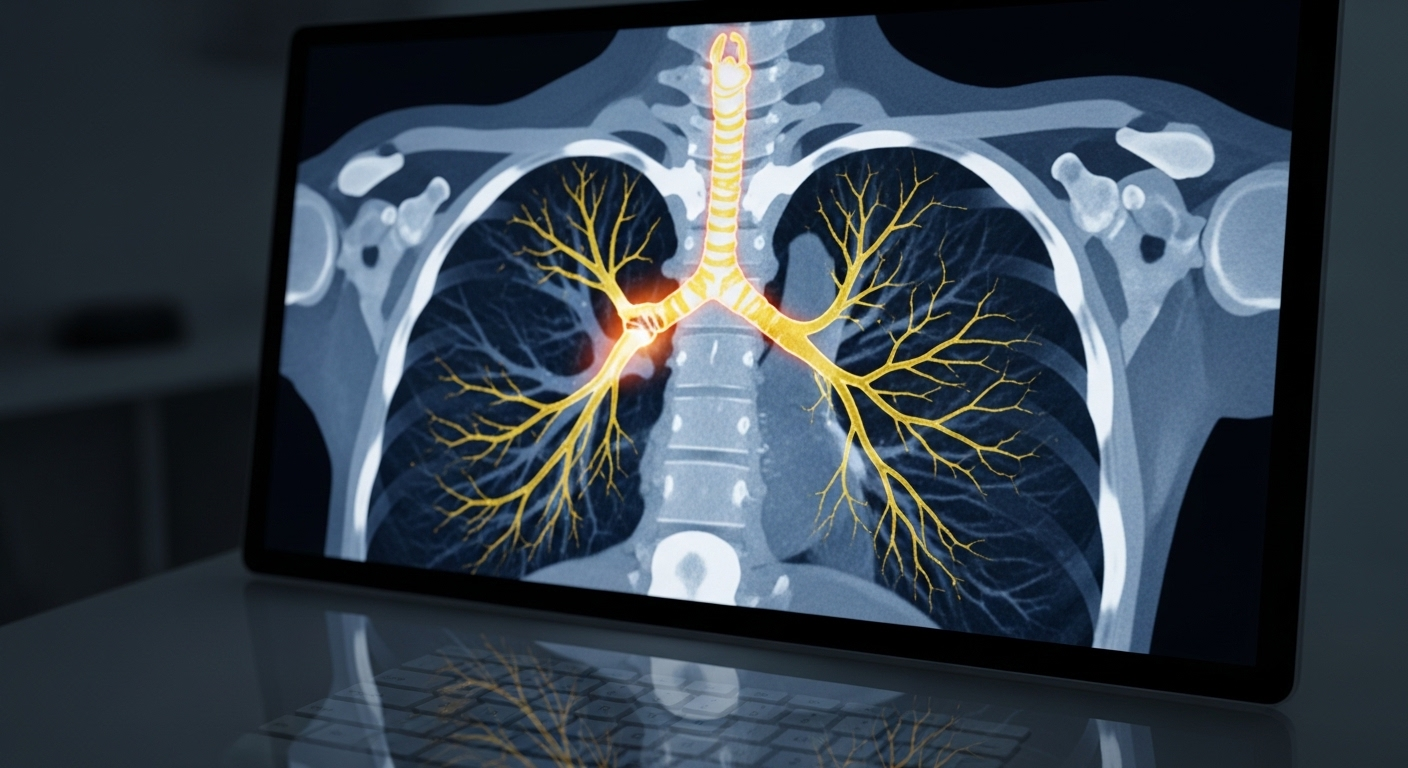

Chụp X-quang phổi: Đây là bước đầu tiên, có thể phát hiện các dấu hiệu gợi ý như xẹp phổi, hình ảnh viêm phổi tái phát, hay những tổn thương nhu mô phổi cũ.

Chụp cắt lớp vi tính (CT) lồng ngực: CT mang lại hình ảnh chi tiết hơn rất nhiều về cấu trúc phế quản và nhu mô phổi. Đặc biệt, **CT dựng hình 3D** là công cụ cực kỳ giá trị, nó giúp chúng ta đánh giá chính xác vị trí, mức độ và hình thái đoạn hẹp phế quản, cũng như mối liên quan với các mạch máu và cấu trúc xung quanh – thông tin tối quan trọng cho kế hoạch phẫu thuật.

Bệnh nhân này đã có nhiều năm sống chung với di chứng hẹp phế quản nặng sau khi điều trị lao phổi từ rất lâu. Anh ấy đã phải nhập viện nhiều lần vì xẹp phổi tái phát và những đợt suy hô hấp cấp tính. Mỗi lần như vậy, anh ấy chỉ được điều trị các triệu chứng, không tìm ra gốc rễ vấn đề. Tình trạng thiếu oxy kéo dài khiến cơ thể anh xanh xao, tím tái, cuộc sống gần như đình trệ. Mãi cho đến khi được thăm khám chuyên sâu và thực hiện CT dựng hình 3D, chúng tôi mới phát hiện một đoạn phế quản lớn bị hẹp khít như sợi chỉ, gây tắc nghẽn nghiêm trọng.